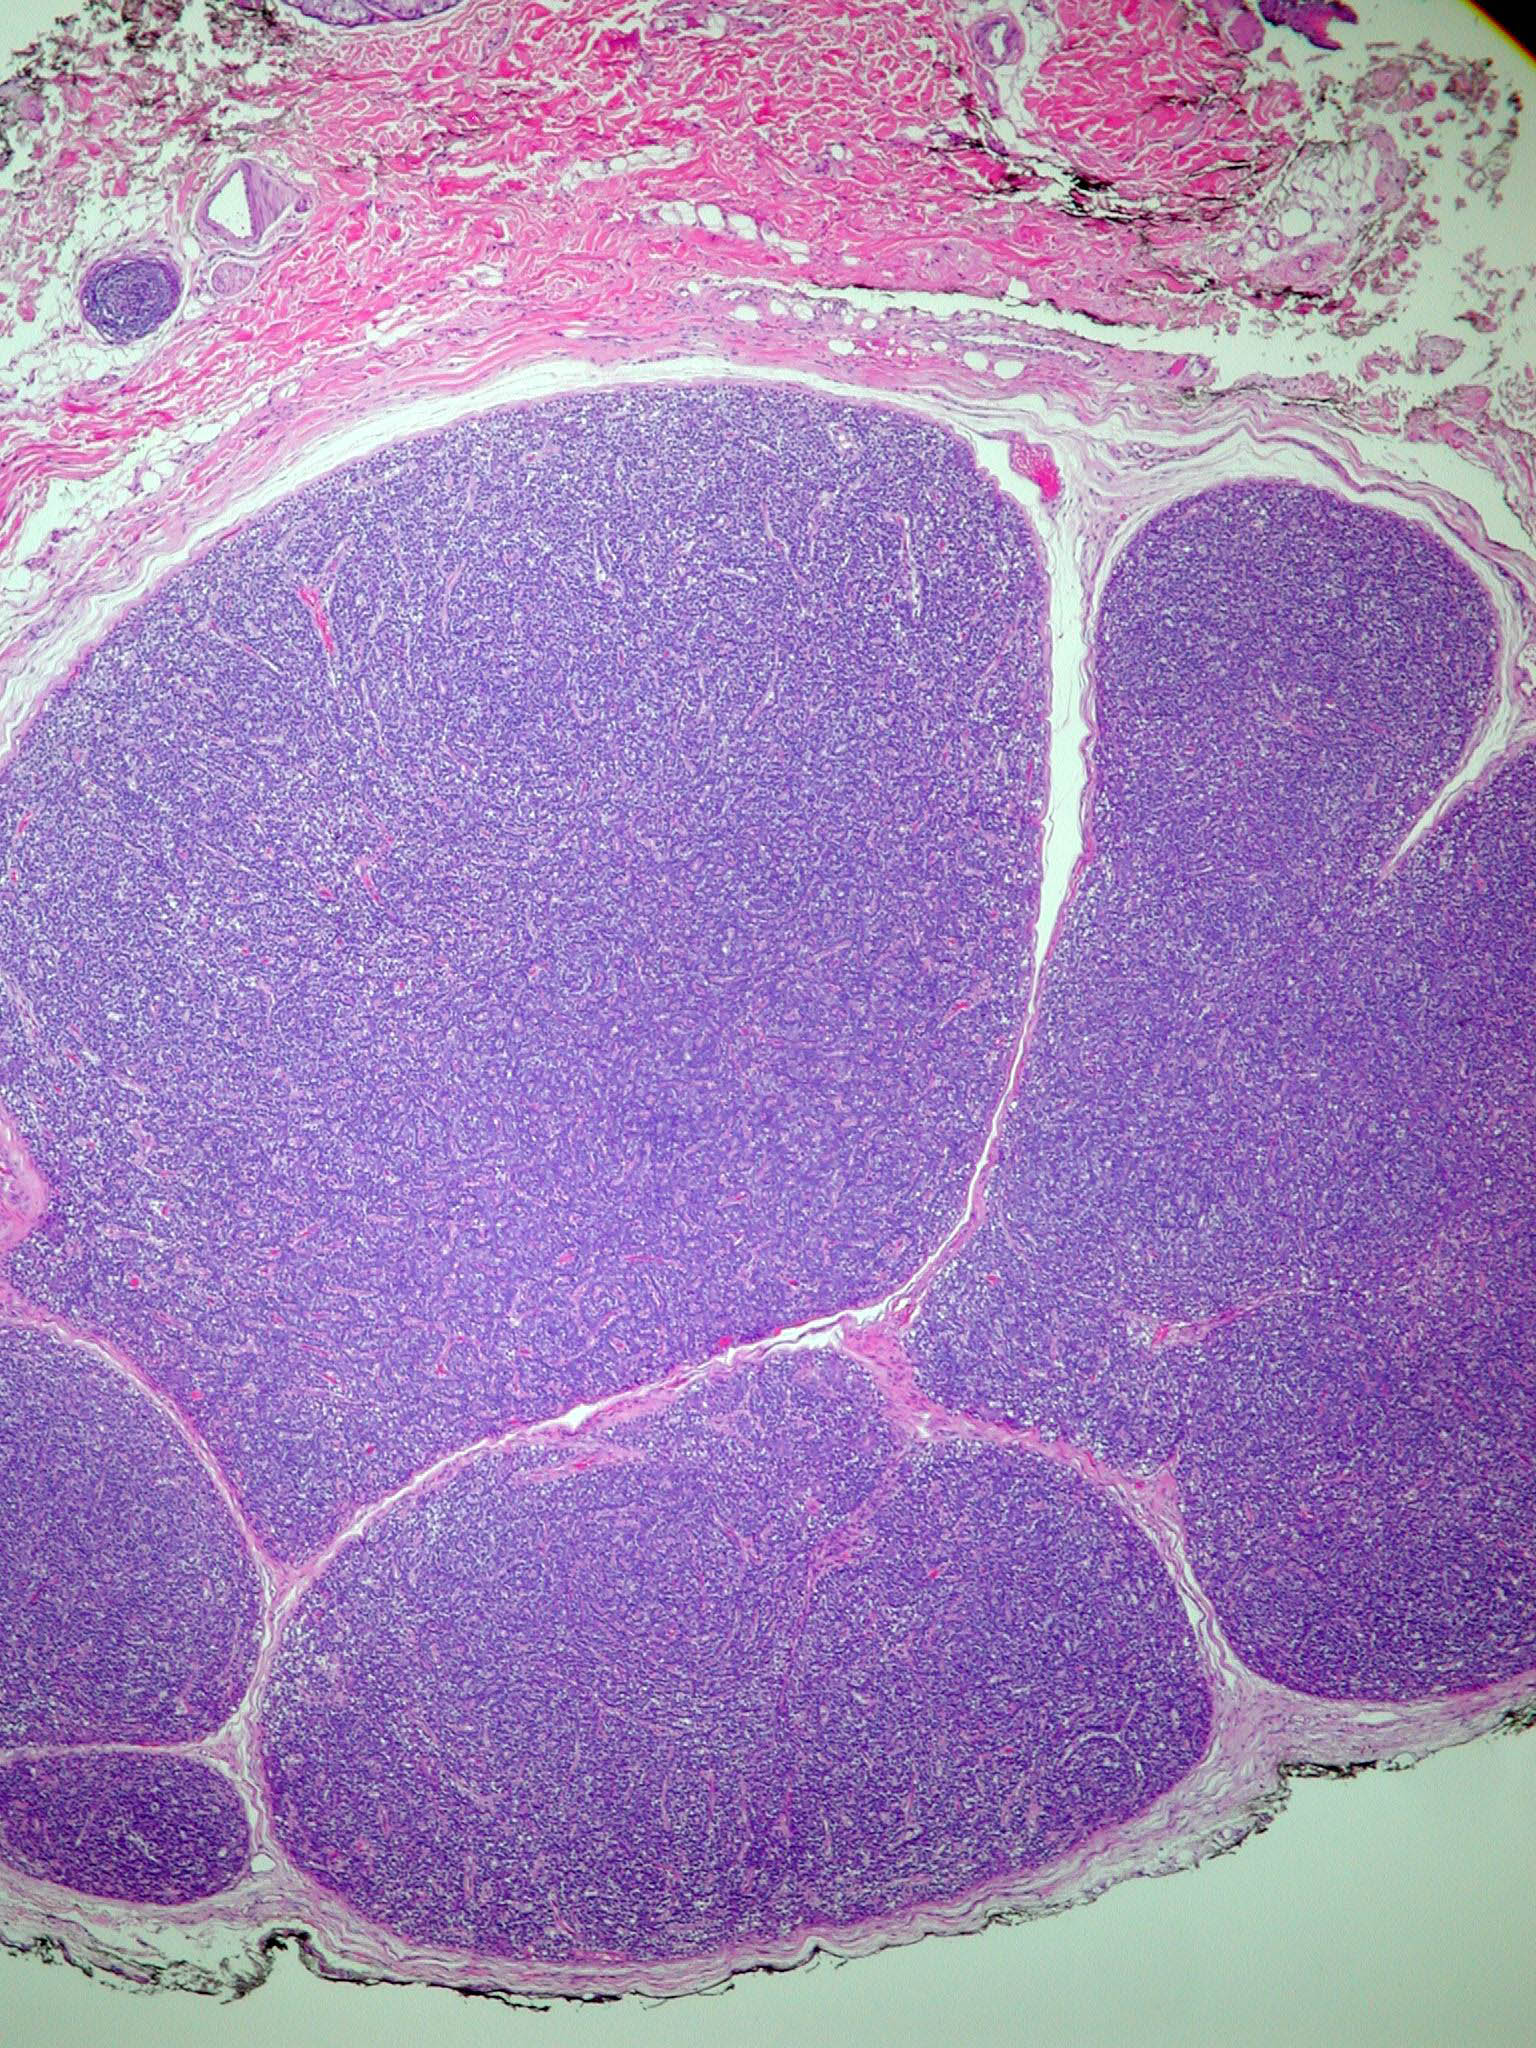

Spiradenoma=ورم غدي عرقي

OLYMPUS DIGITAL CAMERA